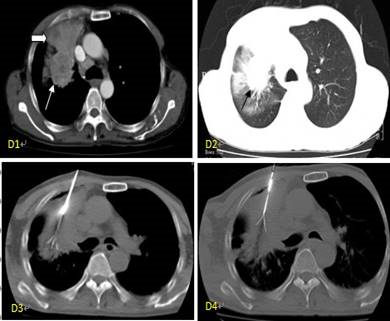

肿瘤射频消融治疗是一种杀伤肿瘤较多而损害机体较轻的肿瘤微创切除治疗方法。肿瘤细胞的特点之一是对热的耐受能力比正常细胞差,该疗法就是根据此特点,应用射频热效应引起组织细胞凝固性坏死的原理而达到消除肿瘤的目的。实施射频消融后,在消融电极的周围形成一个边界清晰近似球形的凝固坏死区,该区域覆盖的肿瘤组织被毁损灭活。凝固坏死的组织部分被人体吸收,这些坏死组织由于其细胞免疫表型的变化而具有瘤苗作用,因此发挥特殊的抗癌作用,并强化患者的免疫功能。

适应症:

可用于人体器官良、恶性实体肿瘤的治疗,目前临床应用较多的是:肝癌、肾癌、肺癌、肝脏和胸部的转移性肿瘤。对于不能手术切除的上述原发性或者转移性晚期肿瘤、不能承受放疗化疗的实体肿瘤患者,均可接受射频消融治疗。